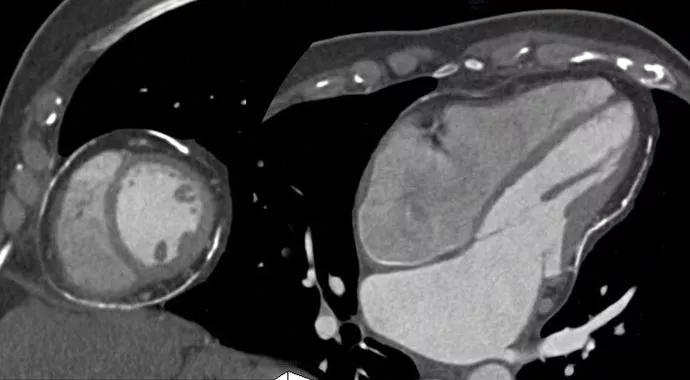

Pericarditis can be tricky to diagnose. Inflammation of the sac around the heart causes symptoms that often resemble other cardiac and pulmonary diseases. Imaging modalities from chest X-ray to MRI can help confirm a diagnosis. But accurate, evidence-based guidelines for pericardial disease have not been available. Until now.

A recent expert consensus statement “Multimodality Cardiovascular Imaging of Patients with Pericardial Disease,” has been issued by the American Society of Echocardiography, in conjunction with other major cardiovascular imaging societies. Allan Klein, MD, Director of Cleveland Clinic’s Center for the Diagnosis and Treatment of Pericardial Diseases, chaired the writing group of 15 U.S. authors — which included four other Cleveland Clinic experts.

“There is a strong demand for evidence-based guidelines to help clinicians diagnose and stage pericardial disease,” says Dr. Klein. “Physicians in all settings need to understand its spectrum of presentation, as well as how to identify the presence of inflammation and calcification in order to provide timely, appropriate treatment.”

Pericarditis, says Dr. Klein, is “an equal-opportunity disease.” It affects patients of all ages, from teenagers to older adults, including many with systemic lupus erythematosus or recent open heart surgery. The etiology may be infective, auto-immune, post-myocardial infarction, autoreactive or idiopathic. It may be acute, recurrent or constrictive. Symptoms are often puzzling, and diagnosis may be complicated by the condition’s appearance in combination with myocardial or valve disease. (As an example of the guidelines’ diagnostic insights, Dr. Klein offers this pearl to help identify constrictive pericarditis: “Have the patient stand or sit upright, then look for distended veins in the neck and an elevated jugular venous pulse. These are clear clinical signs.”)

“Imaging-guided treatment of pericarditis is undergoing a renaissance,” Dr. Klein observes. “Our goal in developing these guidelines is that the disease become more widely recognized and appropriately treated so that patients can feel better and get back on their feet.”